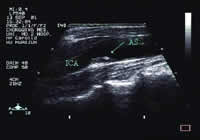

图1 通心络治疗前

图2 通心络治疗后

图1与图2比较,通心络治疗后斑块无明显变化,周围散在低回声物质消失。